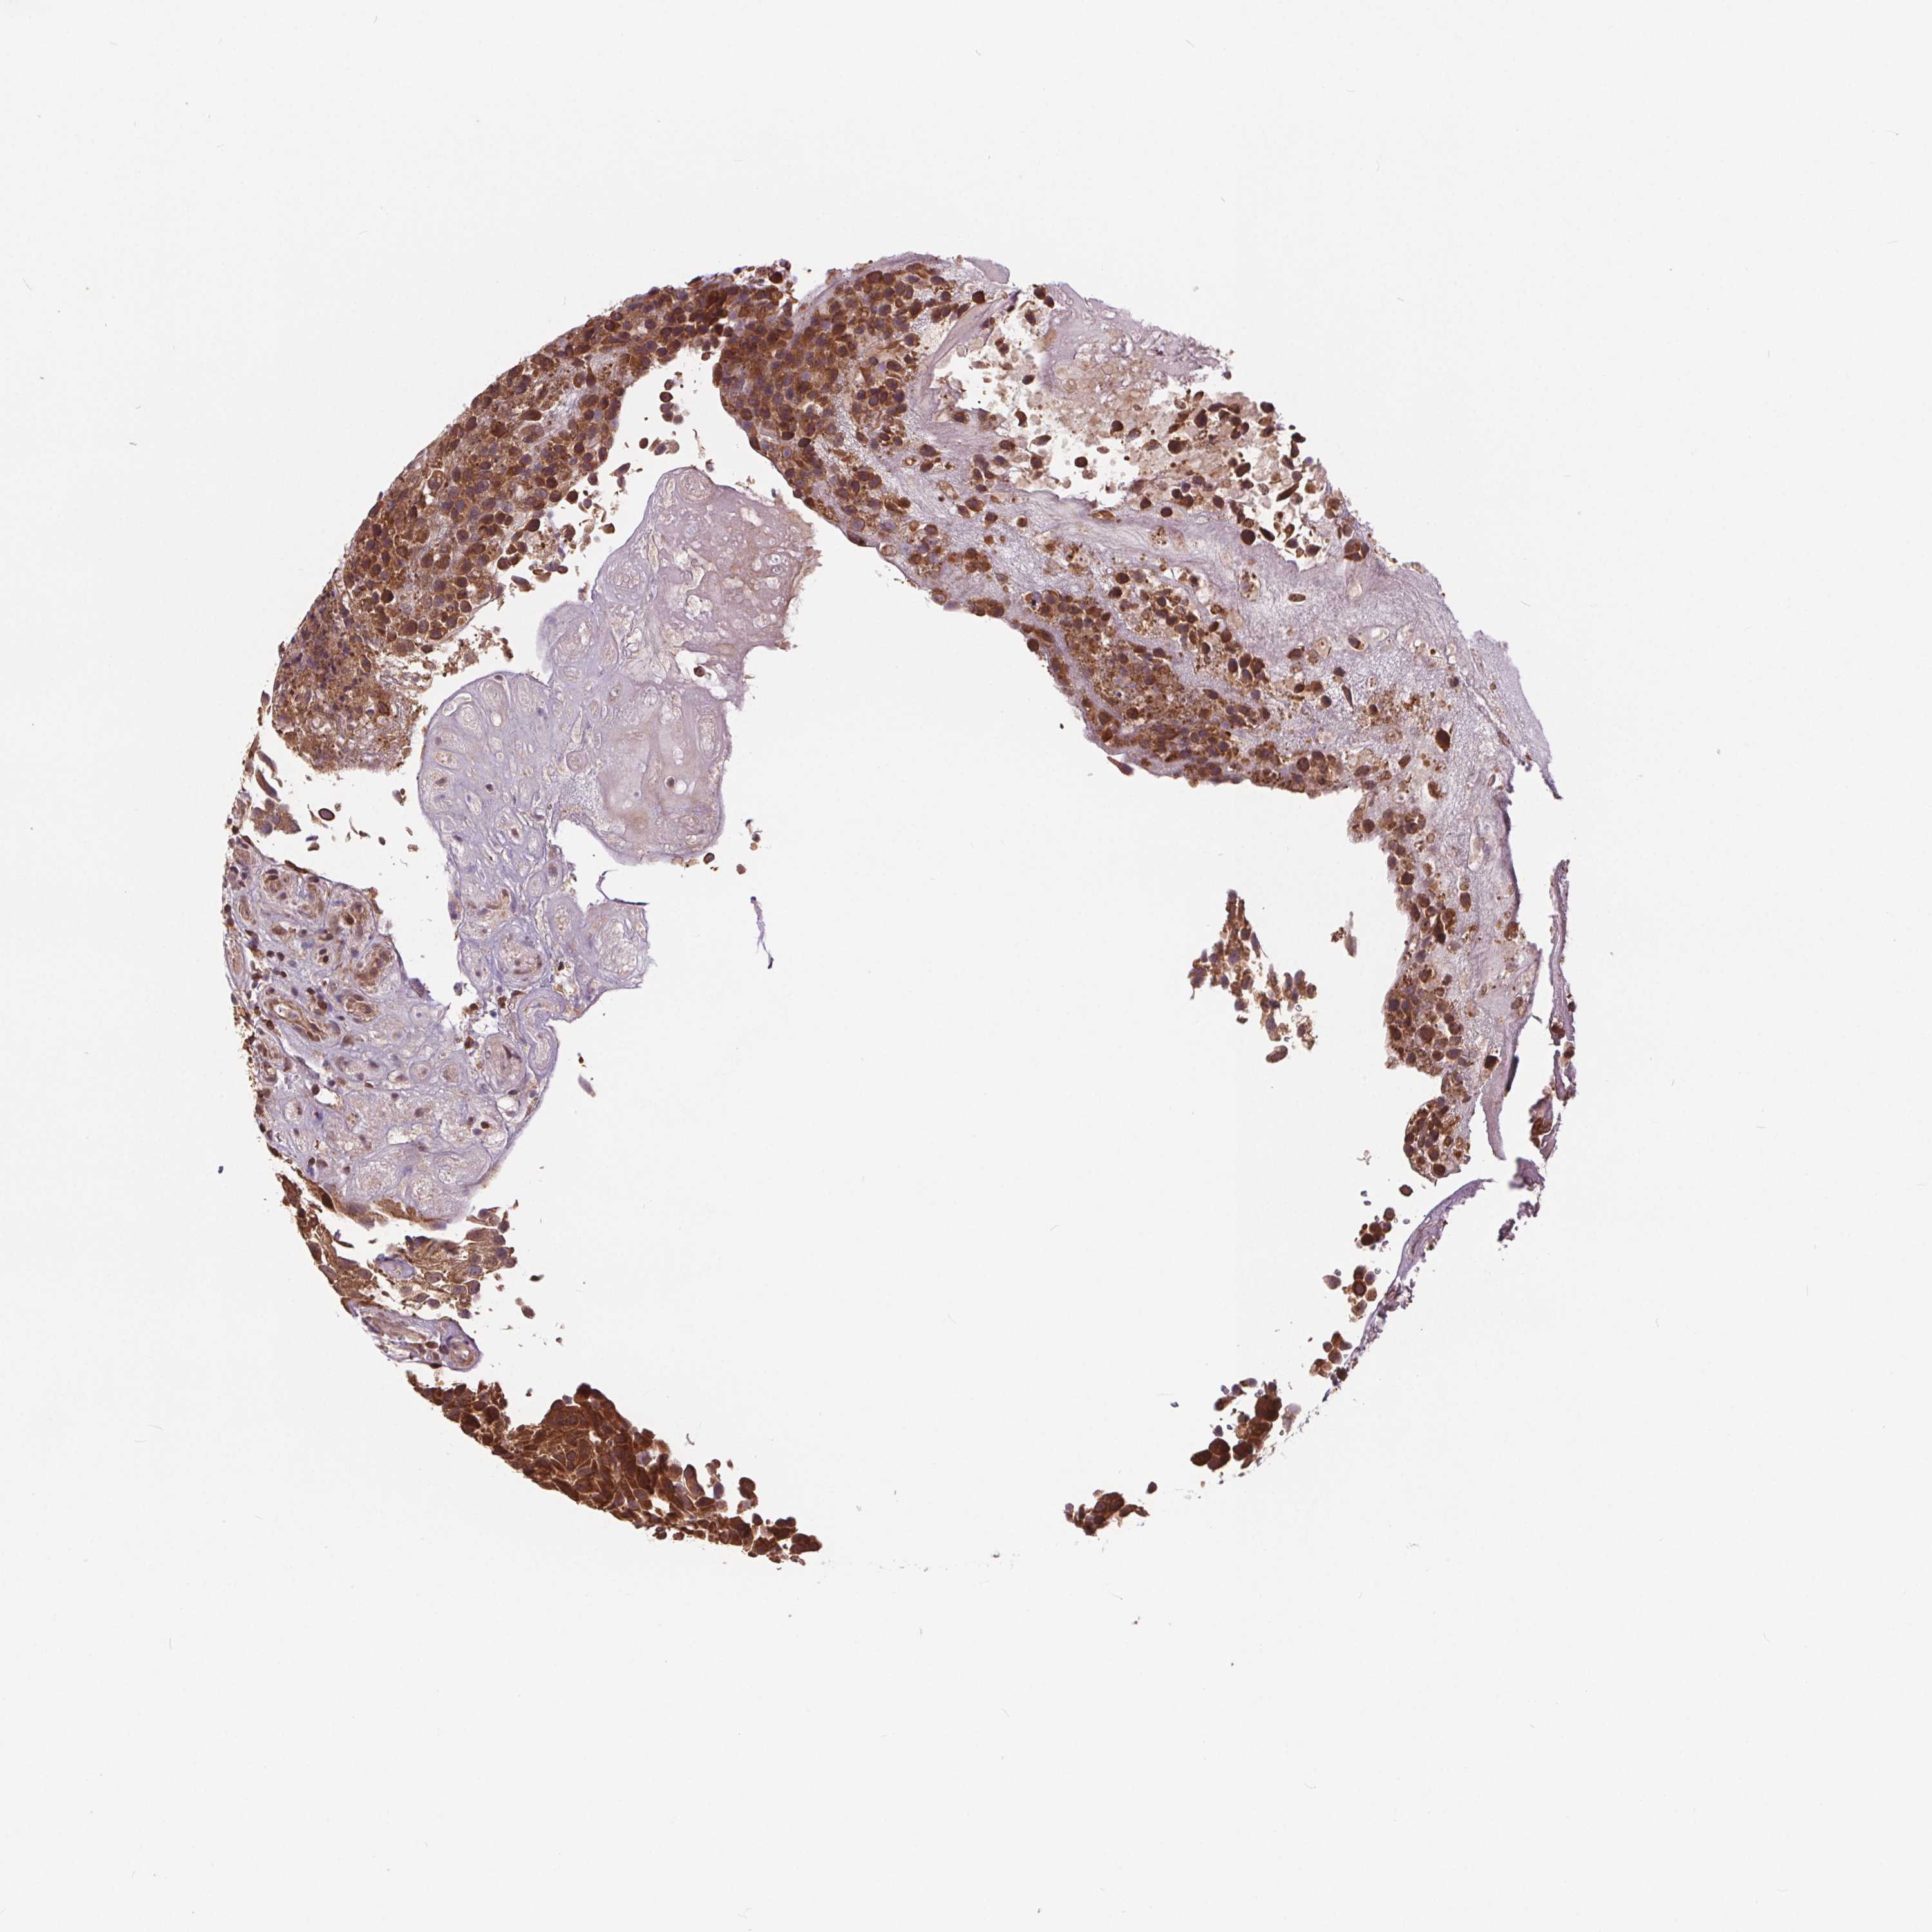

UROTHELIAL CANCER - Protein expressioni

A mouse-over function shows sample information and annotation data. Click on an image to view it in a full screen mode. Samples can be filtered based on level of antibody staining by selecting one or several of the following categories: high, medium, low and not detected. The assay and annotation is described here.

Antibody stainingi

Antibody staining in the annotated cell types in the current human tissue is reported as not detected, low, medium, or high, based on conventional immunohistochemistry profiling in selected tissues. This score is based on the combination of the staining intensity and fraction of stained cells.

Each image is clickable and will lead to virtual microscopy that enables deeper exploration of all samples and also displays staining intensity scores, fraction scores and subcellular localization as well as patient and tissue information for each sample.

Antibody HPA065302

Antibody CAB069903

Staining

High

Medium

Low

Not detected

Intensity

Strong

Moderate

Weak

Negative

Quantity

>75%

75%-25%

<25%

None

Location

Nuclear

Cytoplasmic/membranous

Cytoplasmic/membranous,nuclear

Urothelial carcinoma, High grade

Urothelial carcinoma, Low grade